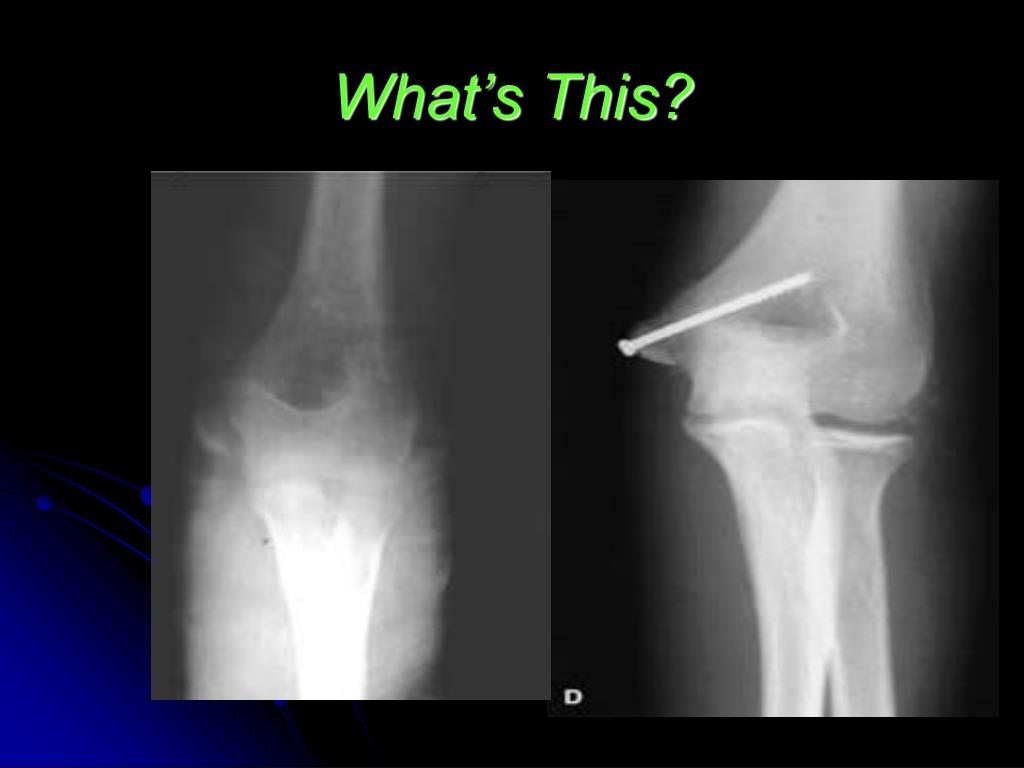

49. What’s This?

50. Medial Epicondyle Fracture • Usually seen in adolescent boys • Do not involve the joint surface • Check for ulnar nerve injury • 50% associated with dislocation – • If diplacement < 4mm – backslab • If displacement > 5 mm - pinned